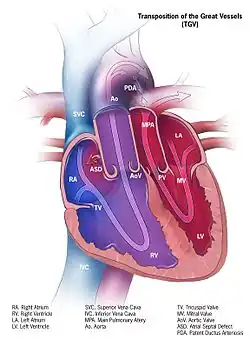

- пороки сердца (врождённые и приобретённые);